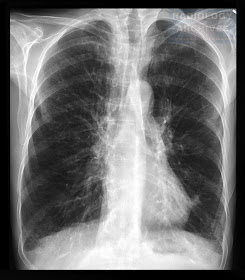

Χρόνια Αποφρακτική Πνευμονοπάθεια (ΧΑΠ)

Chronic Obstructive Pulmonary Disease (COPD)